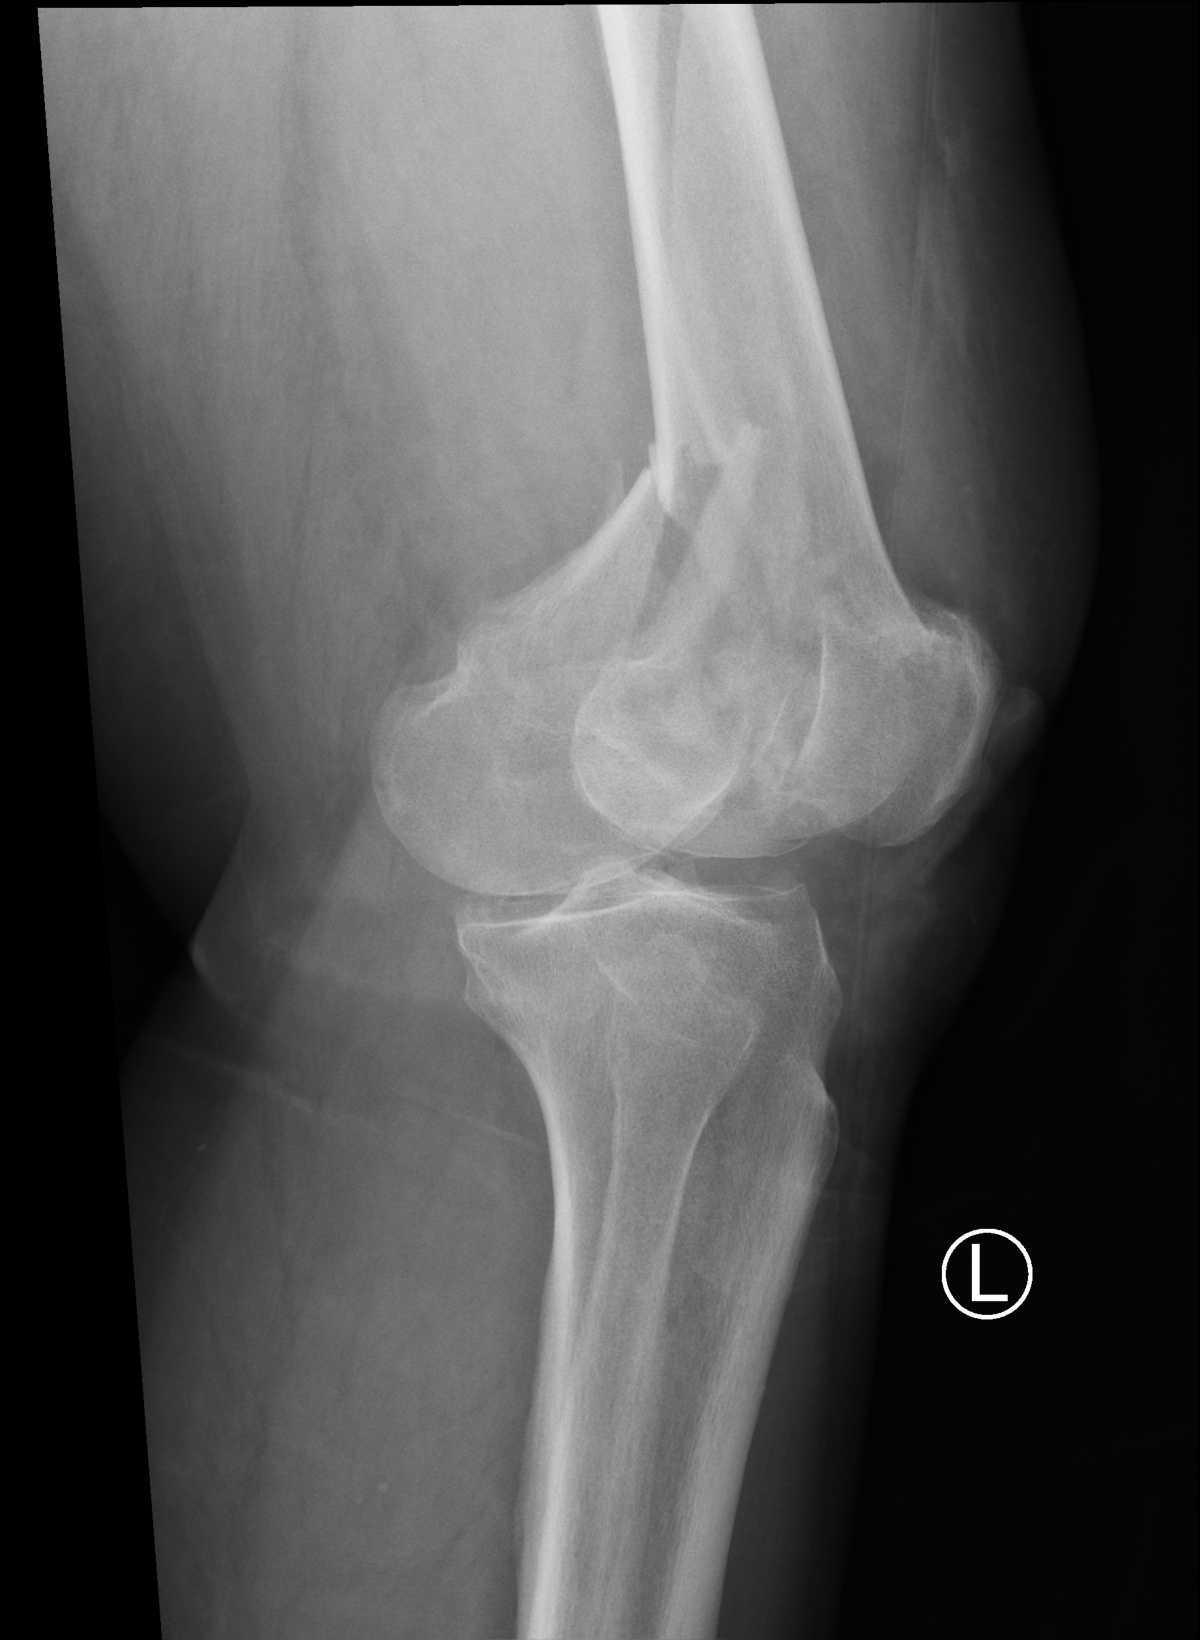

Fracture de l’extremite inferieure du femur

Kevan English, Radiopaedia.org. From the case rID: 183735

Avis chirurgical pour traitement chirurgical.